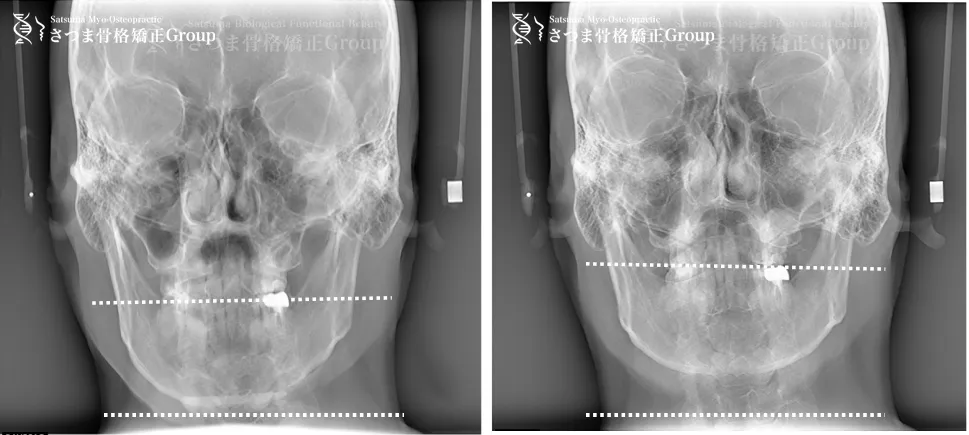

30代男性 リンタロー様

BEFORE

下顎やや左方シフト

下顎位の滑落

The mandible shows a slight leftward shift

with instability (slippage) of the mandibular position.

AFTER

中顔面の短縮

下顎の左方シフト改善、

正中誘導

下顎位の改善

整顔率の向上

correction of the leftward mandibular shift; guidance toward the facial midline; improvement in mandibular positioning; increased facial balance and symmetry.